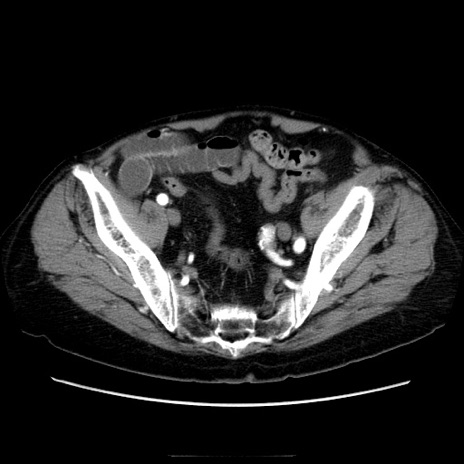

症例21(横断像)

冠状断像

【症例】70歳代男性

【主訴】腹痛

【現病歴】肝硬変・肝細胞癌にてかかりつけの方。約9時間前に食後より腹痛出現。症状が徐々に増悪し、嘔吐出現したため来院。

【既往歴】肝硬変、肝細胞癌(RFA、TACE後)

【身体所見】意識清明、表情苦悶様、BT 36℃、BP 129/78mmHg、P 88bpm、SpO2 97%(RA)、右上腹部から心窩部にかけて圧痛あり、反跳痛なし、筋性防御あり。

【データ】WBC 5800、CRP 0.16